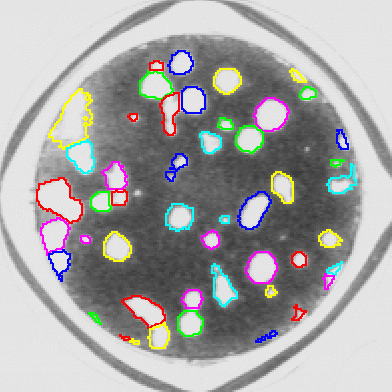

Axons: Finding cell nuclei with our software

Axons: Finding cell nuclei with our software.

automatically count cell nuclei in cytoplasm in images with a low signal-to-noise ratio.

Cytology: automatically count cell nuclei in cytoplasm in images with a low signal-to-noise ratio.